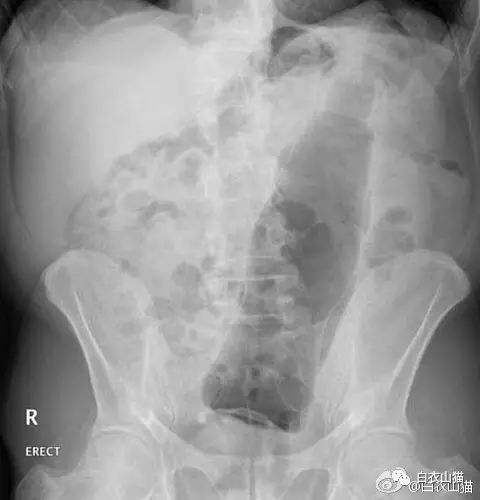

医生给他检查的时候,发现已经有腹膜炎症状,怀疑肠梗阻,拍了个片子,就是上面那个片子:一条大黄鳝在肚子里。

上面是前几年一名患者大肠里的黄鳝。

上面是近年医院里的一个病人,也是乙状结肠新鲜穿孔。医生给他开腹手术,从腹腔里取出来的5条泥鳅和一条黄鳝。